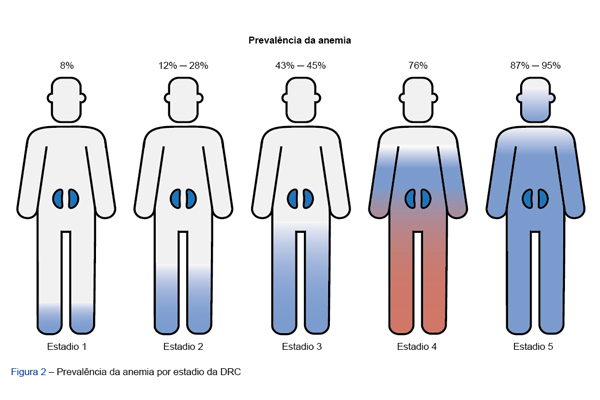

O envelhecimento populacional tem-se traduzido no aumento de prevalência de doenças crónicas como a doença renal crónica. A anemia &e...